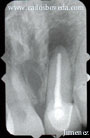

Foto # 2

Radiografía Inicial (Marzo,31/99)

El examen radiográfico reveló un tratamiento de conducto defectuoso en la obturación y ausencia de poste o muñón artificial en el diente #21. El tratamiento ideal de este diente una vez reobturado adecuadamente el conducto sería: Colocar un poste o muñón artificial y prepararlo para recibir una corona definitiva. En este caso se consideró que el tratamiento más ideal sería utilizar postes y muñones estéticos de resina reforzada con fibra de vidrio cementados con cementos resinosos en combinación con una corona de porcelana. La corona existente en el diente #31 también presentaba un aspecto grisáceo, por lo que se le sugirió al paciente reemplazarla con otra corona de cerámica. Adicionalmente, el color de los dientes naturales del paciente era A 3.5 (Guía Vita), por lo que se le realizó blanqueamiento dentario por dos semanas con el Night White Bleaching antes de restaurar las coronas de los dientes 31 y 21.